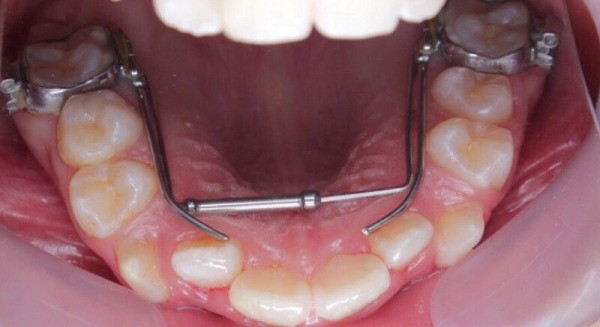

Có thể nong hàm dưới được không?

Phương pháp nong hàm chủ yếu tập trung vào vòm hàm trên, nhưng trong một số trường hợp đặc biệt, bác sĩ cũng có thể thực hiện mở rộng hàm dưới. Tuy nhiên, quá trình này khá phức tạp hơn và phụ thuộc vào từng tình huống cụ thể.

Đối với hàm dưới, kỹ thuật nong hàm thường ít phổ biến hơn do cấu trúc xương khó khăn hơn và nguy cơ biến chứng cao hơn. Thay vào đó, các phương pháp điều chỉnh khác như phẫu thuật hàm hoặc chỉnh nha phối hợp có thể được chỉ định.

Trong các trường hợp trẻ nhỏ, bác sĩ có thể xem xét mở rộng cả hai hàm để đạt được sự cân đối tốt nhất cho toàn bộ khuôn mặt và chức năng cắn khớp.